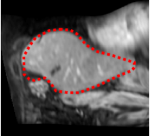

An example of CT/CBCT and MR/CBCT registration results are shown in figures 3 and 4, respectively. For both cases, the CBCT image (first column) was acquired intra-operatively after needle insertions and was employed as a reference for image registration. The pre-operative image is displayed before registration (second column), after PM-EA (third column) and after PM-EA+Evo (fourth column). The occurrence of patch shifts is reported for each spatial direction in panels (m–o): for each histogram, the shift with maximal occurrence is shown by the red dashed line. For panels (a–l), a ROI — manually defined on the CBCT image/encompassing the liver — is shown using red dash lines. Our visualization shows an improved correspondence of the contour of the liver with the manually defined liver boundary when the PM-EA solution is employed (see 3(c,g,k) and 4(c,g,k)). Moreover, an even better correspondence of the contour is observable using the PM-EA+Evo solution (see 3(d,h,l) and 4(d,h,l)).

Trans.

[X-Y]

CBCT

(a)

CT / No registration

(b)

CT / PM-EA

(c)

CT / PM-EA+Evo

(d)

Sag.

[X-Z]

(e)

(f)

(g)

(h)

Cor.

[Y-Z]

(i)

(j)

(k)

(l)

(m)

(n)

(o)